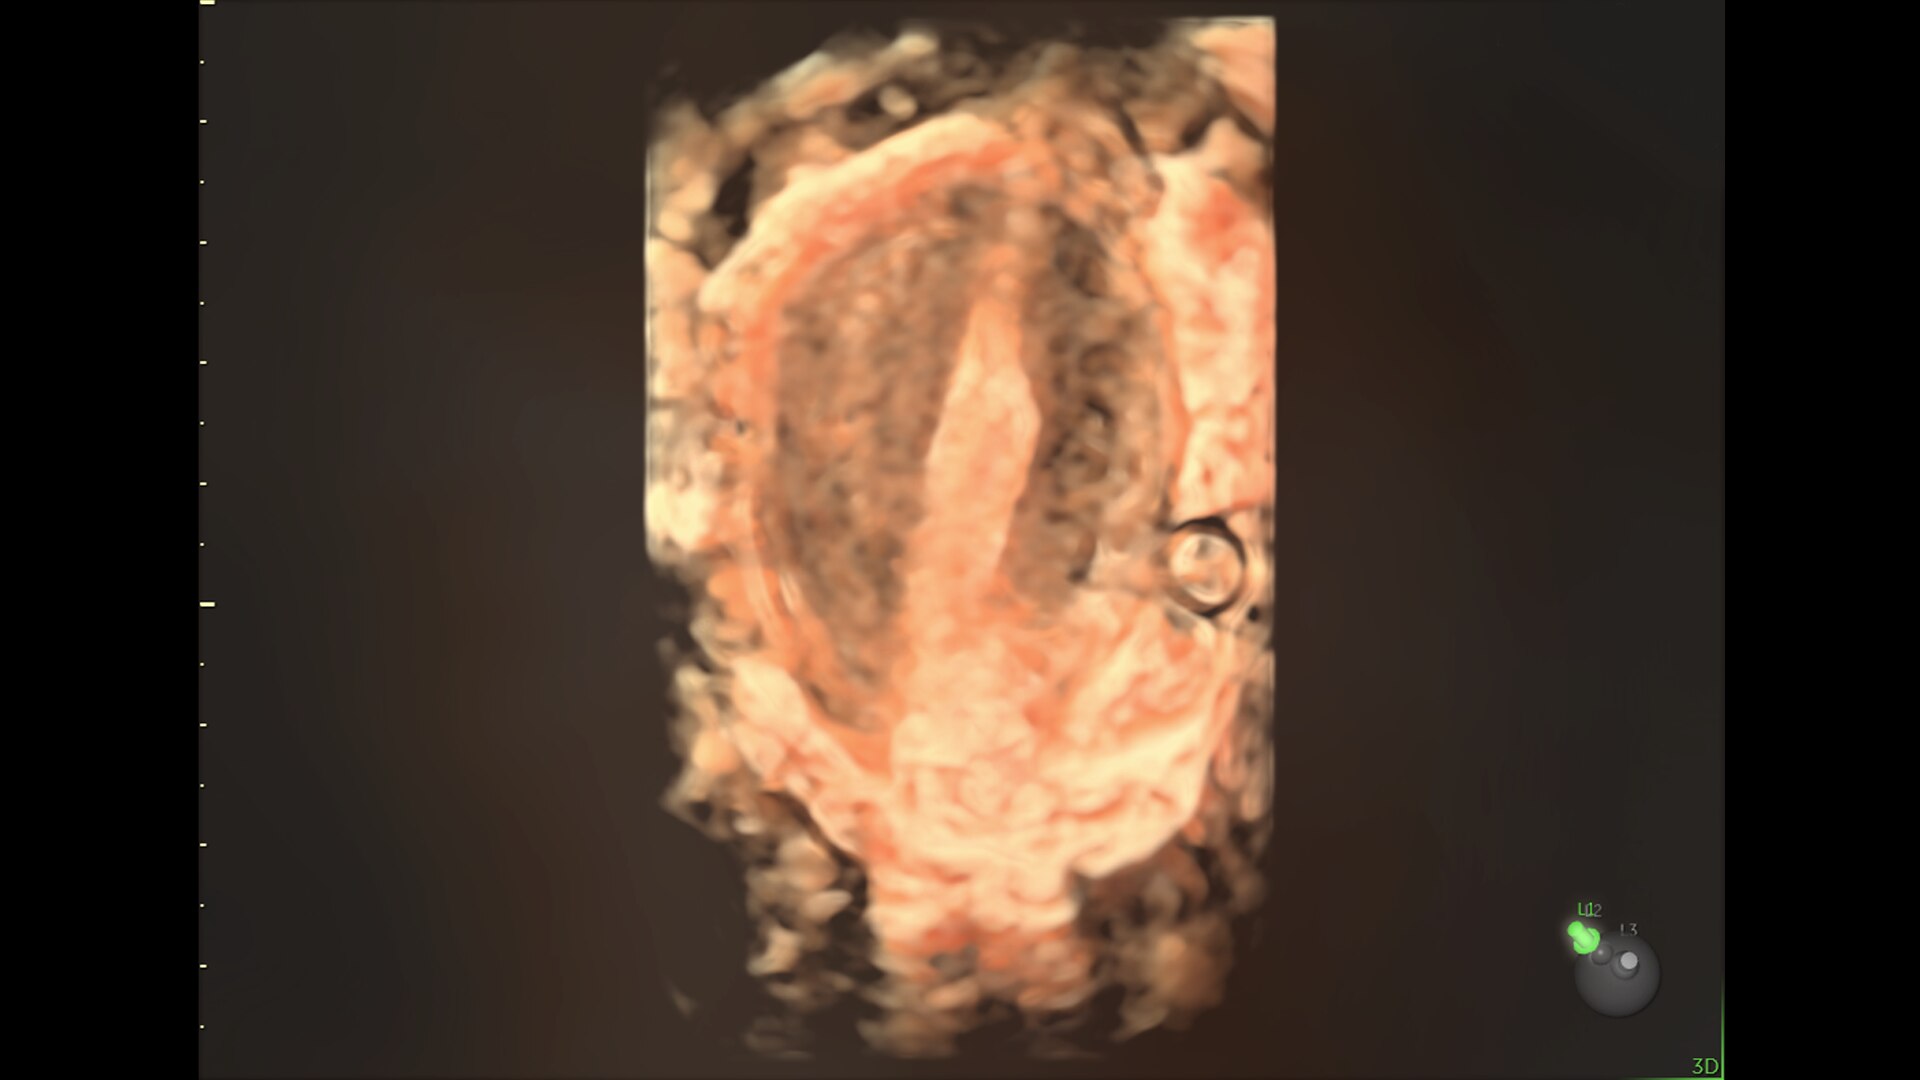

FETAL HEART EVALUATION

Get to the Heart of the Matter

Identifying fetal cardiac abnormalities earlier means you can intervene sooner, plan for delivery, and potentially improve outcomes. The Voluson Expert 22 provides a full solution of progressive tools, to help distinguish the tiniest structures with stunning clarity to provide patient answers faster.